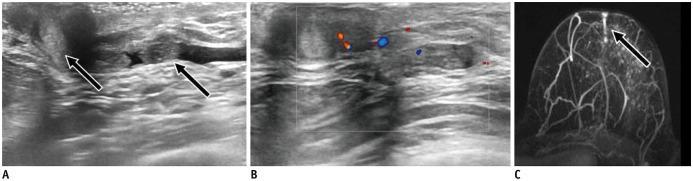

Ultrasound (US) is an attractive diagnostic approach to identify both common and uncommon nipple pathologies, such as duct ectasia, nipple abscess, nipple leiomyoma, nipple adenoma, fibroepithelial polyp, ductal carcinoma (restricted to nipple), invasive carcinoma, and Paget's disease. US is the reliable first-line imaging technique to assess nipple pathologies. It is useful to identify and characterize nipple lesions. Additionally, we have presented the mammography and MRI outcomes correlated with histopathologic features for the relevant cases.